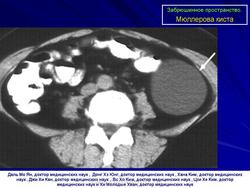

Забрюшинное пространство. Патология.